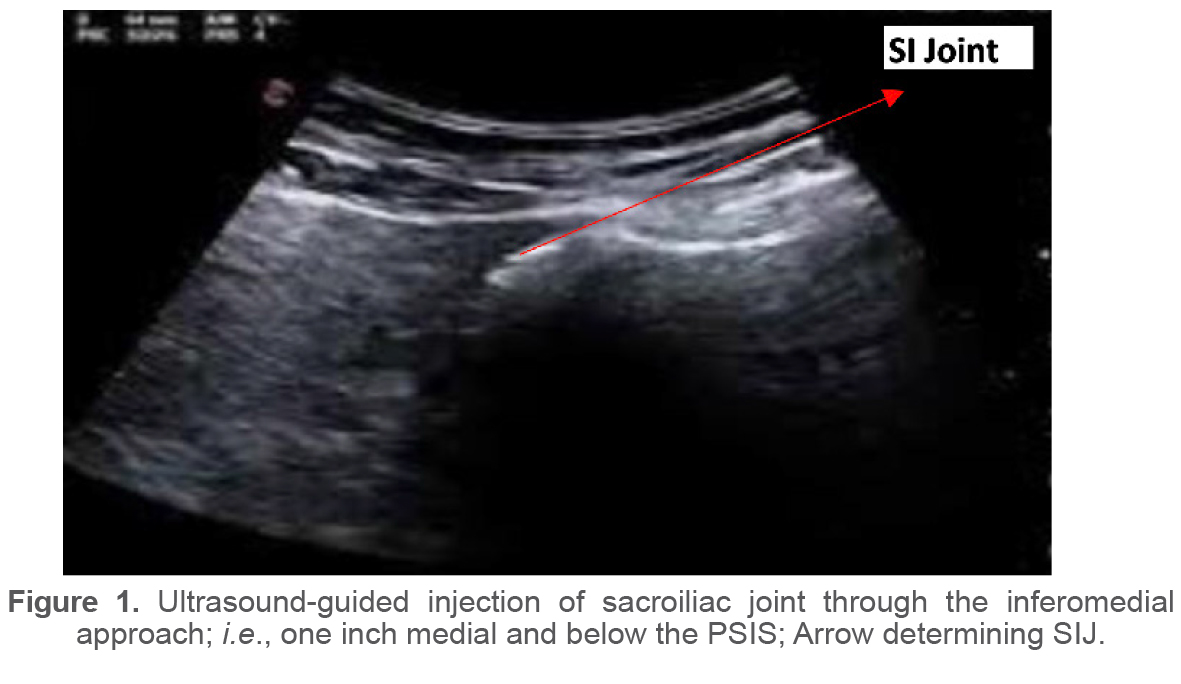

For US guidance, the transducer was positioned transverse to the sacral hiatus (sacral cornea) and then moved slightly lateral to reach the sacrum’s outer edge until the joint appeared in the US field (in-plane method). The treatment groups in this survey were unknown to the patients, the assessor physician, and the physician who performed the injections. The syringes used looked identical and were wrapped in an aluminum envelope. All injections were performed under sterile conditions by a PM&R specialist with 10 years of experience in musculoskeletal injections using the spinal needle Gauge 22 through an inferomedial approach, i.e, one inch medial and below the PSIS (Figure 1). Initially, each patient received 2 ml of 2.5% bupivacaine intra-articular injection as a confirmatory test for SIJ dysfunction. 2.5 ml of dextrose 20% solution was injected into the prolotherapy group, while 2.5 ml of triamcinolone 40 mg/ml was injected into the steroid group. A program of stretching exercises and Acetaminophen consumption was recommended to control potential post-injection reactions.

Figure 1. Ultrasound-guided injection of sacroiliac joint through the inferomedial approach; i.e., one inch medial and below the PSIS; Arrow determining SIJ.